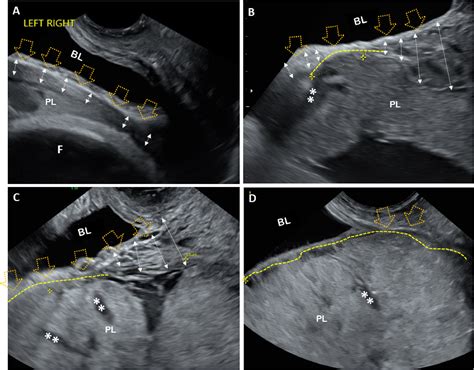

During the early stages of pregnancy, the fertilized egg travels to the uterus and implants itself. The placenta develops wherever that implantation occurs. If it implants on the front wall of the uterus, it is classified as an anterior placenta. Conversely, a posterior placenta attaches to the back wall, and a fundal placenta attaches near the top. An anterior placenta ultrasound typically reveals this position during your mid-pregnancy morphology scan, usually conducted between 18 and 22 weeks.

When you arrive for your scan, the sonographer will use a handheld device called a transducer. By applying a water-based gel to your abdomen and moving the transducer over the surface, the machine transmits sound waves that create images of your baby and the surrounding structures. During this process, the technician will identify the placenta's location to ensure it is not covering the cervix.

You might wonder if an anterior placenta makes a C-section more likely or affects the labor process. The truth is that for the vast majority of cases, it does not. The placenta’s location on the front wall does not generally interfere with the baby’s ability to descend into the birth canal. The primary concern medical teams look for during an anterior placenta ultrasound is placenta previa—a condition where the placenta covers the cervix. If the placenta is located in the anterior position but is far enough away from the cervix, it is perfectly safe for a vaginal delivery.

⚠️ Note: If an ultrasound identifies a "low-lying" placenta, regardless of whether it is anterior or posterior, your doctor will likely schedule follow-up scans to monitor if it moves upward as the uterus grows.